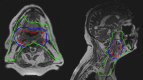

Purpose: Purpose of this study is to evaluate plan quality on the MRIdian (Viewray Inc., Oakwood Village, OH, USA) system for head and neck cancer (HNC) through comparison of planning approaches of several centers.

Methods: A total of 14 planners using the MRIdian planning system participated in this treatment challenge, centrally organized by ViewRay, for one contoured case of oropharyngeal carcinoma with standard constraints for organs at risk (OAR). Homogeneity, conformity, sparing of OARs, and other parameters were evaluated according to The International Commission on Radiation Units and Measurements (ICRU) recommendations anonymously, and then compared between centers. Differences amongst centers were assessed by means of Wilcoxon test. Each plan had to fulfil hard constraints based on dose-volume histogram (DVH) parameters and delivery time. A plan quality metric (PQM) was evaluated. The PQM was defined as the sum of 16 submetrics characterizing different DVH goals.